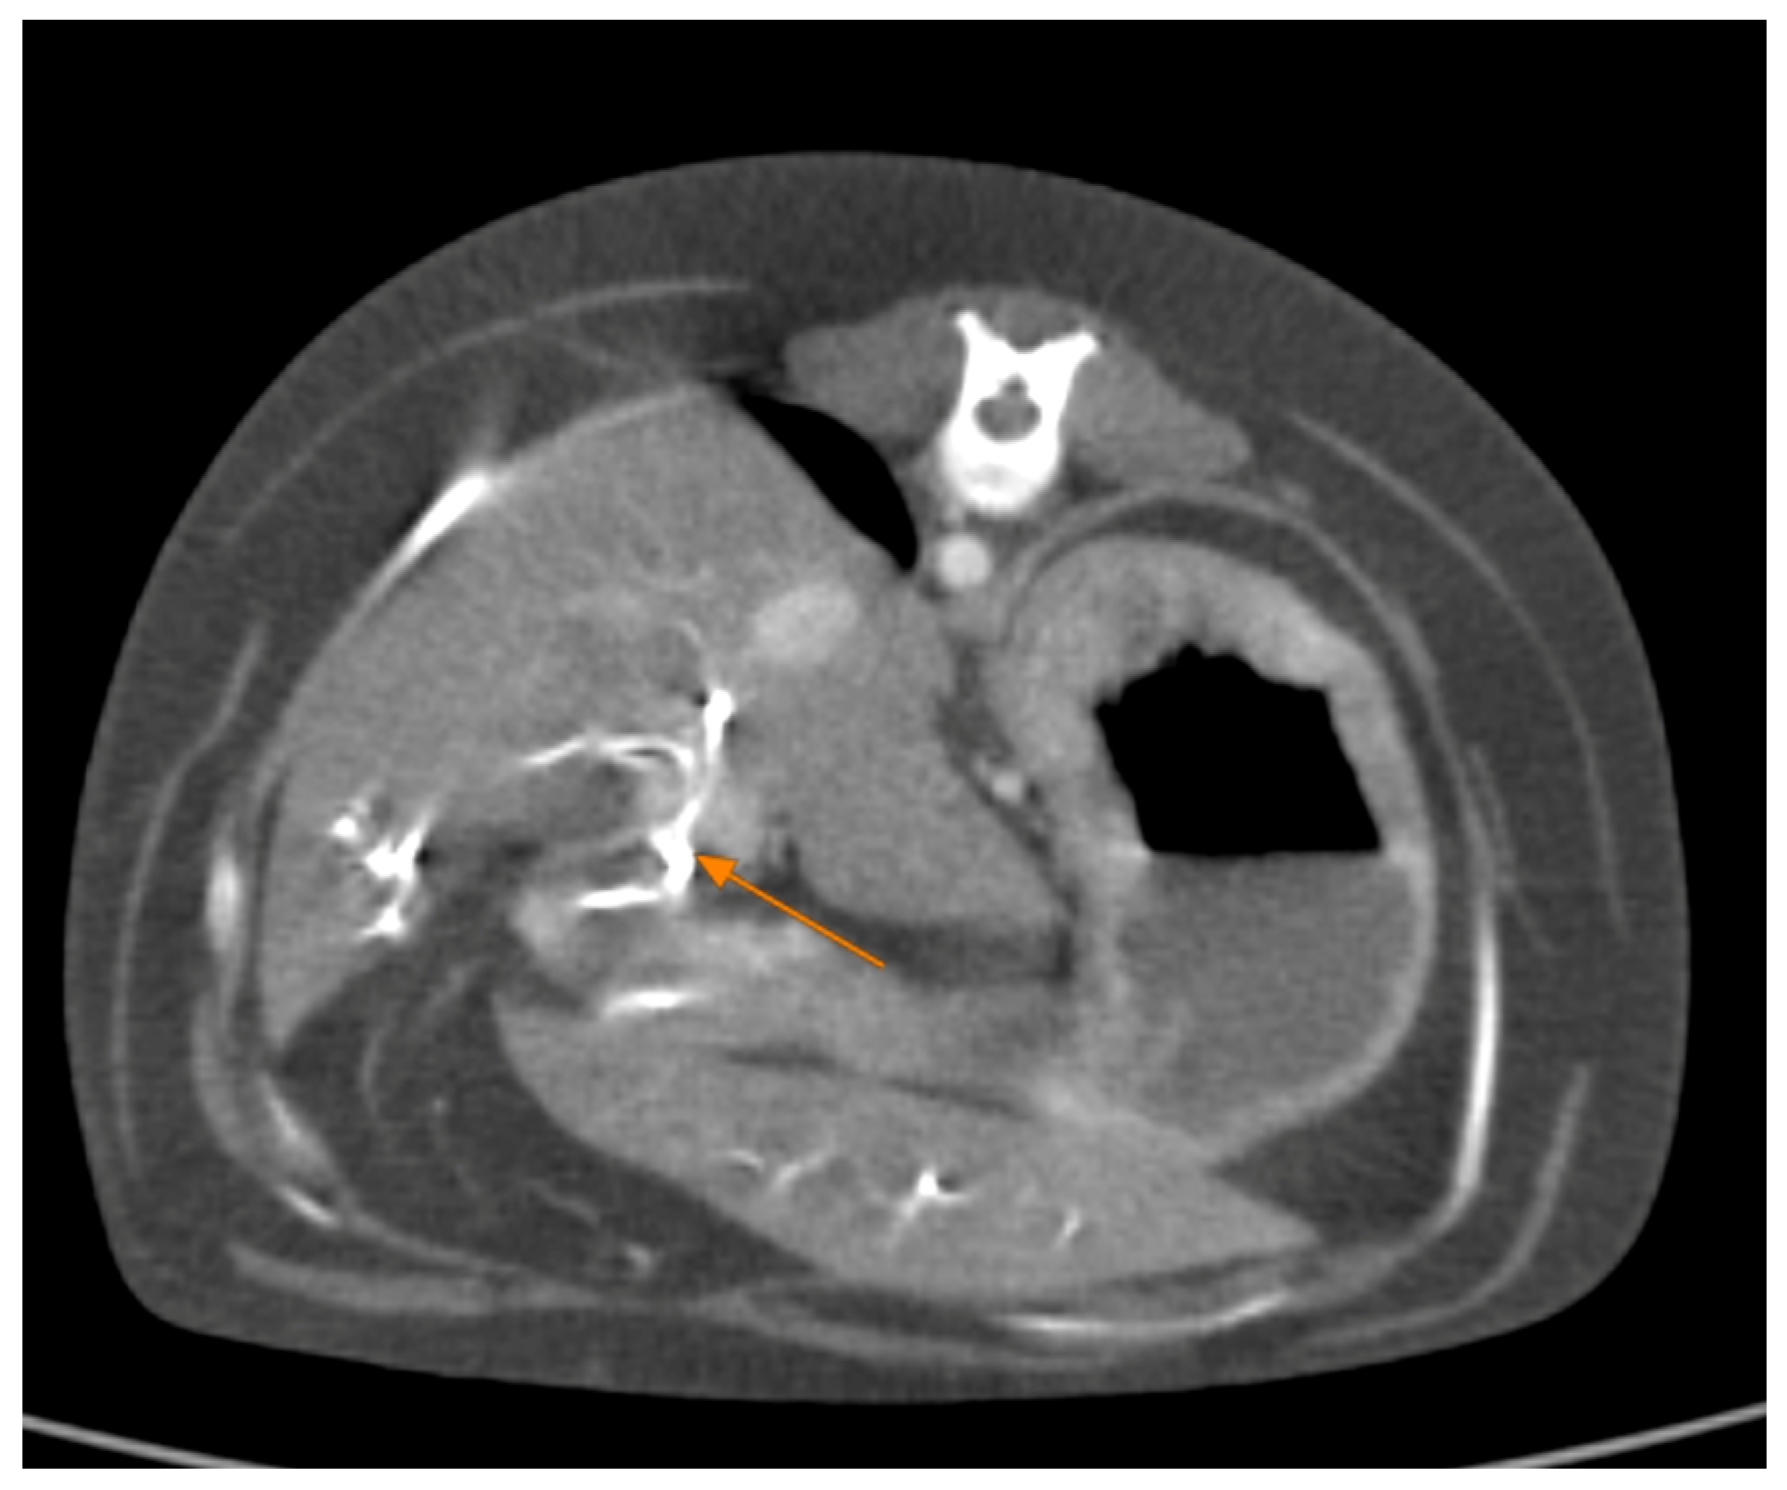

Contrast-enhanced CT of the abdomen performed 48 h into the investigation, confirmed the presence of high-density material (barium sulfate) within the intrahepatic and extrahepatic biliary ducts. The CT also provided detailed information about the pancreas: the pancreatic parenchyma was irregularly enlarged and heterogenous, with regions of mottled hypoattenuation. Mild peripancreatic fat stranding (inflammation of surrounding fat) was evident, and multiple ill-defined, round hypoattenuating areas were present within the pancreas, consistent with abscesses or pockets of necrosis (Figure 5 and Figure 6). The common bile duct was markedly distended and filled with hyperattenuating contrast material (barium), confirming duodenobiliary reflux in cross-sectional detail (Figure 7).

Figure 7. Abdominal contrast CT (axial plane). The common bile duct (outlined by orange arrows) is markedly dilated and packed with high-density barium sulfate.